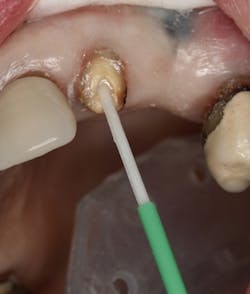

Figure 1: Occlusal image of finished root canal prep after gutta-percha removal

The root canal on No. 10 was completed using the WaveOne Gold system (Dentsply Sirona). Upon completed obturation, care was taken to remove only excess gutta percha from the canal using a warmed endodontic plugger. Removal extended approximately 4 mm to 5 mm into the canal space (figure 1).